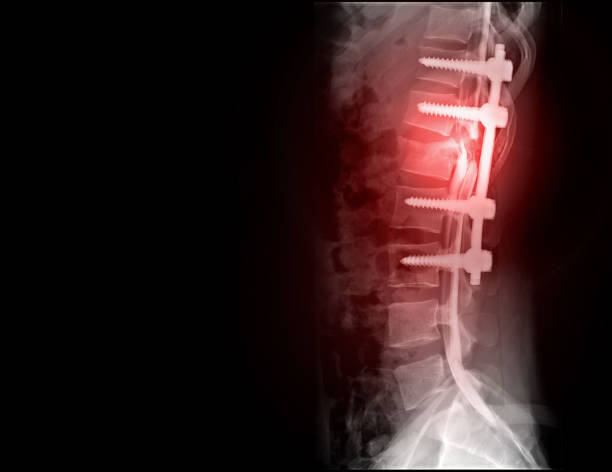

척추관협착증은 다른 척추 질환에 비해 퇴계 정도가 매우 심한 질환으로, 퇴행이 심할수록 근육과 인대가 더욱 뭉쳐지고 더 많은 압력을 가하게 됩니다. 이 때문에 근육과 인대를 풀어주는 것이 중요하며, 이를 위한 가장 적합한 운동이 걷기입니다.